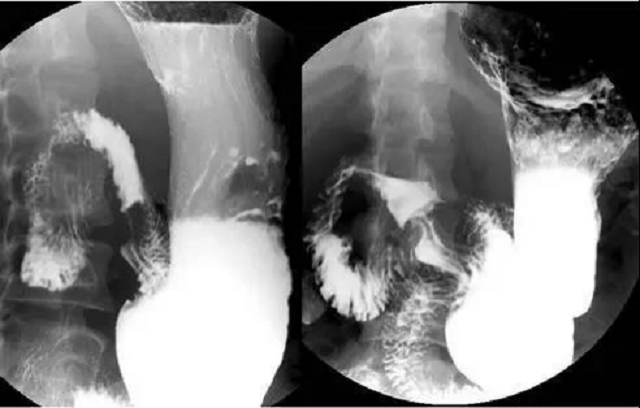

鋇餐全稱(chēng)鋇餐造影,即消化道鋇劑造影,是指用硫酸鋇作為造影劑,在X線照射下顯示消化道有無(wú)病變的一種檢查方法。與鋇灌腸不同,鋇餐造影是用口服的途徑攝入造影劑,可對(duì)整個(gè)消化道,尤其是上消化道進(jìn)行更清晰的放射性檢查。用于消化道檢查的鋇餐是藥用硫酸鋇(即硫酸鋇的懸濁液),因此它不溶于水和脂質(zhì),所以不會(huì)被胃腸道黏膜吸收,因此對(duì)人基本無(wú)毒性。

鋇餐檢查則是患者需先服下3-5克產(chǎn)氣粉,使胃充分?jǐn)U張后,再服下一定量醫(yī)用純硫酸鋇混懸液,使胃充盈。當(dāng)X線透過(guò)人體時(shí),利用顯示器間接觀察被鋇劑充盈的胃的形態(tài)、大小、位置及蠕動(dòng)情況等,并進(jìn)行攝像,結(jié)合臨床表現(xiàn)做出綜合判斷。對(duì)于部分臨床癥狀和X線征象均不典型的患者還須結(jié)合其他檢查。

1、可以在X線下觀察粘膜是否光滑及胃的皺襞是否完整,還可了解胃腸的蠕動(dòng)情況。

2、如果鋇劑本身顆粒大,涂抹不均勻,觀察不細(xì)心,則一些微小病變?nèi)菀走z漏。

3、X線鋇餐造影只能觀察形態(tài)、蠕動(dòng)等情況,不能活檢,不知道局部病理情況。

鋇餐檢查時(shí)患者一般無(wú)痛苦和并發(fā)癥,容易接受。雖然傷害小,但是由于此項(xiàng)檢查時(shí)口服發(fā)泡劑或向腸道注氣,使胃腸道內(nèi)既有高密度的鋇劑,又有低密度的氣影,不容易獲得陽(yáng)性結(jié)果,也就是說(shuō)檢查準(zhǔn)確率不高,容易誤診。